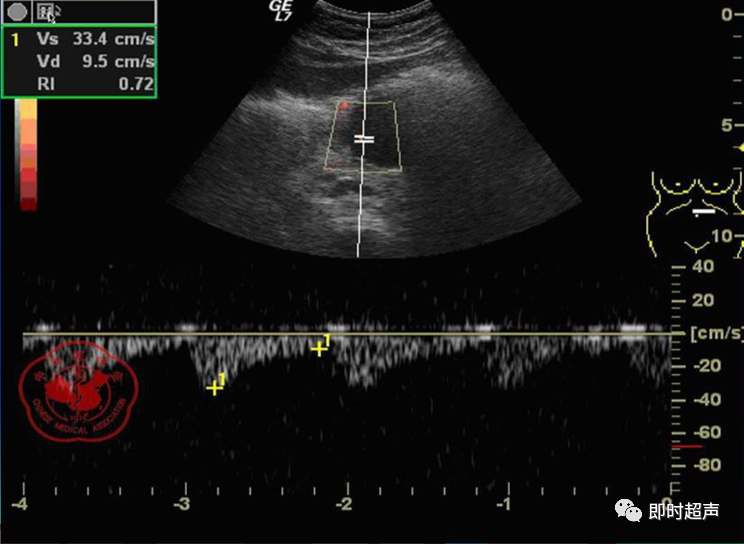

• GIST的发病机制与KIT信号通路的激活有关。• KIT是一种酪胺酸激酶跨膜受体蛋白,未经“装配”过的KIT蛋白是一种非活化的单体,参与细胞膜形成。几乎所有GIST都表达了KIT蛋白,而且大多突变的KIT基因保留了表达KIT蛋白的特性。c-kit内的突变主要见于恶性病例,特别是外显子11的点突变,还有外显子9、13和17,可以导致本质的或配体独立的c-kit激活,引发细胞的无序增殖和凋亡。这些具有功能的突变是GIST发病机理的关键,并且与肿瘤的恶性程度和预后较差相关。• GIST约75%发生于50岁以上老年人,中位年龄为58岁,无明显差异。• 可以发生在消化道从食道到肛门的任何部位,偶尔可原发于网膜、肠系膜和腹膜后,约50%发生在胃,25%发生在小肠,不足10%发生于食管、结肠及直肠。大体观察:肿块多境界清楚,类圆形,结节状,部分有假包膜。切面灰白、灰红,质韧,部分质嫩呈鱼肉状,伴有出血、坏死、囊性变。• 肿瘤组织主要由两种细胞组成,一种为长梭形细胞,细胞质丰富,嗜酸性,细胞核呈梭形或杆状;另一种为上皮样圆形或多角形细胞,细胞肥胖,胞质少。两种瘤细胞常呈束状、编织状或旋涡状排列。• 部分病例细胞异型明显,核分裂象增多,可见病理性核分裂象和瘤巨细胞。梭形细胞界不清楚,胞质丰富,淡染,轻度嗜伊红或略嗜碱,可有纤细、长梭形、短梭形或胖梭形、卵圆形,可见核仁。细胞核两端钝圆,部分病例胞质呈空泡状,位于核一端形成核端空泡胞,多呈交叉束状、旋涡状、席纹状及栅栏状排列。上皮样细胞胞浆丰富或透亮,多呈弥漫片状、束状或巢状排列。肿瘤间质可有出血、囊性变、坏死及黏液变,可见炎性细胞浸润。CD34抗原是一种115kd的糖基化蛋白,50%~80% GIST的CD34表达为阳性,CD34对鉴别GIST和典型的平滑肌瘤,神经鞘瘤还是非常有用的标记物,因后两者的CD34一般是阴性的。但CD34在诊断GIST上其特异性受到限制,一般情况下CD34多与CD117联合应用,方能提高GIST的诊断率。• 与肿瘤大小、发生部位、肿物与肠壁的关系以及肿瘤的良恶性有关。• 肿瘤较小者(直径小于2cm)常无症状,往往在体检和其它手术时无意中发现。• 肿瘤发生于胃肠道腔内时大多表现为呕吐、腹痛及消化道出血,而发生于胃肠道腔外的则主要表现为腹部包块。• 最常见的临床症状是中上腹部不适、腹部肿块及便血。• 对于临床发现的消化道(包括肠系膜、网膜、后腹膜)实体肿瘤,在排除其他常见肿瘤后,才考虑GIST。目前,诊断GIST有三条标准:③肿瘤组织具有梭形细胞和上皮样细胞两种基本细胞成分的病理学特征。这是诊断GIST金标准。CD117阳性者或CD117阴性而CD34阳性者,且伴平滑肌和神经双向分化或无分化者,可诊断为GISTs;以Desmin和SMA强阳性,而CD117阴性诊断为平滑肌肿瘤;以S-100阳性,CD117、Desmin、SMA均阴性诊断为神经鞘瘤。• GISTs的分型与组织学良恶性的关系:研究证实GISTs非单一分化的肿瘤,具有多向分化。• 当前GISTs的良性、交界性和恶性判断标准多参照Amin等提出的标准:②交界性:核分裂<5/50HPF,但肿瘤>5cm;• 另外研究显示,平滑肌型大多数为良性,少数为交界性和恶性,神经源型为恶性,双向分化亚型和未分化型为交界性和恶性,提示GISTs的分化型与其良恶性之间有一定关系。• 胃间质瘤早期多局部侵犯,后期出现肝转移和腹腔内种植,小肠间质瘤早期即可出现转移• 主要有超声扫描(检出率30%左右)、纤维内镜、超声内镜、CT、MRI、普通X• 线检查(胃肠钡餐造影、小肠插管气钡双重造影)、选择性血管造影检查等。• 不同部位的GIST,各种检查方法的敏感性不同。以CT检查为佳,尤其是螺旋CT,分辨率最高,可以三维重建,直接显示肿瘤大小、形态、密度、内部结构、边界,对邻近组织的侵犯也看得很清楚,同时还可观察其他部位的转移灶,有利于分期、鉴别与诊断。• MRI具有多轴成像及反映肿瘤内部成分的优点,尤其是动态扫描及各种新的扫描系列的出现更使其可以普及应用。• DSA检查对于GIST,特别是有消化道出血的患者更有价值。• 上述影像学检查表现并非特异性,与胃肠道平滑肌肿瘤、神经源性肿瘤鉴别困难。明确诊断要依赖病理免疫组化等手段。• 超声图像特征 肿物体积较小者(直径< 5. 0 cm )多为实性病变, 呈类圆形, 边界清晰, 内部回声多为较均匀的低回声。• 肿物体积较大者(直径> 5. 0 cm ) 多为混合性病变,呈不规则圆形或分叶状, 多数边界尚清晰, 以实性为主的病变内部为不均质中低回声伴不规则液性区及斑点状强回声; 以囊性为主的病变囊壁较厚,有分隔, 部分囊腔内可见点状、团状低回声。CDFI显示肿物实质回声内血流均较丰富。病例1:患者男, 62岁。自扪腹部包块2月余,包块增大20天就诊。查体:腹部平坦,无腹壁静脉曲张,无胃肠型及蠕动波,腹肌软,剑突下5cm处及左肋缘下可触及一质韧包块,大小约15*12cm,活动度差,边界尚清,包块深压痛,全腹无反跳痛。化验检查AFP:3.66(1.09-8.04)ng/ml,CEA:2.85(0-5)ng/ml。体格检查:一般情况良好,全腹软、平坦,腹部无压痛。超声检查:患者仰卧位时左上腹于胰尾前方可见一大小约6. 1 cm ×5. 8 cm ×5. 3 cm实性均质低回声,形态规则,包膜完整,边界清晰,活动度大;右侧卧时,肿块移至胰头右前方(图1) ;于其内探及丰富血流信号。体格检查:一般情况良好,腹丰满,上腹部有轻压痛,未扪及明显肿块。超声检查:患者仰卧位时左上腹于胰尾前方、脾门处可见一大小约10. 0 cm×8. 8 cm×7. 6 cm 实性低回声(图2) ,形态规则,包膜完整,边界清晰,肿块活动度大;右侧卧时,肿块移至左肝下间隙,回声尚均质;于其内探及较丰富血流信号(图3) 。图3 腹腔低回声肿块位于左肝下间隙,于低回声肿块内探及较丰富血流信号向壁外生长的胃肠道间质瘤, st为胃腔,箭头所指为胃壁, T为向外生的肿瘤• 胃间质瘤的定位准确率要高于十二指肠及小肠间质瘤,这主要是因为胃的解剖位置相对固定,且通过饮水使胃腔充盈,可清晰的显示胃壁的各层结构及肿块与胃壁的关系。肿块多表现为粘膜下、肌层或浆膜下低至中等回声团块,可向腔内、腔外或腔内外生长。但当肿瘤较大或浸润周围脏器时,超声定位仍有困难, 因此,超声如发现上腹部肿块且怀疑来源于胃者,应尽可能嘱其饮水充盈胃腔,并多角度、多切面观察肿块与周围脏器的关系,以提高定位的准确性。• 十二指肠间质瘤的定位亦较准确,但降部的外生性肿块常与胰头粘连而误诊为胰腺肿瘤回声均匀且位置较深的间质瘤亦可能误为胰头周围淋巴结。• 空、回肠间质瘤常因肿块较大,多发,位置不固定而难以定位,往往误诊为腹、盆腔或腹膜后肿瘤,超声检查如发现肿块局部肠壁增厚,肿块与肠道随呼吸同步运动时可作出定位诊断。• GIST的声像图表现有助于其良、恶性的鉴别:良性肿瘤多体积较小,圆形或椭圆形,回声均匀,边界清晰。恶性肿瘤多较大,呈不规则分叶状,回声不均匀,内部易出血、坏死、囊变。• 肿瘤长径与肿瘤内部是否出现无回声区在良、恶性病变之间的差异有统计学意义,是判断良恶性的有效征象。• 如以肿瘤长径>5cm为诊断恶性标准,其敏感性、特异性及准确性均较理想。超声可为临床提供胃肠道间质瘤的部位、大小、边界、回声等较多有用信息,一部分病例可作出定位、定性诊断,并可在术后或复发患者药物治疗期间对其进行动态观察;CDFI方便快捷、无需造影剂即可对间质瘤周边及内部血流进行观察,可为临床医师提供肿瘤血供情况。但未发现腹腔或肝脏转移时,超声判断胃肠道间质瘤性质有一定难度。• 目前临床上对GISTs的治疗效果并不十分满意。治疗仍以手术为主,对无法手术切除或已有转移的GISTs患者进行甲磺酸伊马替尼化疗。• 手术方式取决于肿瘤大小、部位和术中冰冻切片结果等。• 发生在胃的间质瘤,可首选胃大部切除术;发生在十二指肠的间质瘤可行保留胰头的十二指肠切除术或胰十二指肠切除术;发生在小肠的间质瘤可行肿瘤肠段切除术;发生于结肠的间质瘤可行左半或右半结肠切除术;发生于直肠的间质瘤可行肿瘤局部切除术。一般情况下无需淋巴结清扫。• 术后随访监测,复发者单个病灶可考虑手术切除;多发或转移特征者应试行甲磺酸伊马替尼化疗,并监测肿瘤大小及数目的改变。• 随着分子靶点药物进入肿瘤临床,一种小分子化合物———酪胺酸激酶受体抑制剂,美国称为Gleevec,欧洲叫做Glivec(格列卫),在治疗GIST和慢性粒细胞白血病方面有其独特的作用。已知细胞膜表面上皮生长因子受体酪胺酸激酶抑制剂大致分为两大类:一类是小分子化合物;另一类是特异性抗体。利用抑制酪胺酸激酶的活性,对处于增殖期状态的病变具有治疗的作用。Glivec在体外、体内和细胞水平都可强烈抑制酪胺酸激酶的活性,是干细胞因子(SDCF)受体KIT的强抑制剂。• Glivec推荐用量为400mg(4片),每日一次, 3个月为一疗程。如服3个月后无效可加至600mg/d~800mg/d(6~8片)[18];若仍无效果不再增量应停止治疗。• Glivec治疗进展转移的GIST总有效率为50%左右,比传统化疗有效率高十倍以上;肿瘤生长控制率达80%以上,起效最快在服药后24h之内,使症状改善如疼痛缓解;平均起效时间为13周(约3个月)。患者体力状况改善是又一突出效果。2/3患者治疗后无症状可如健康人生活工作。• Brainard等研究发现间质瘤预后差的前两位因素为肿瘤大小和核分裂象,故对于间质瘤直径>5cm和核分裂象>5/50HPF的患者应给予口服Glivec。最近,Liu报道口服Glivec治疗可使85%患者的病情得到控制。